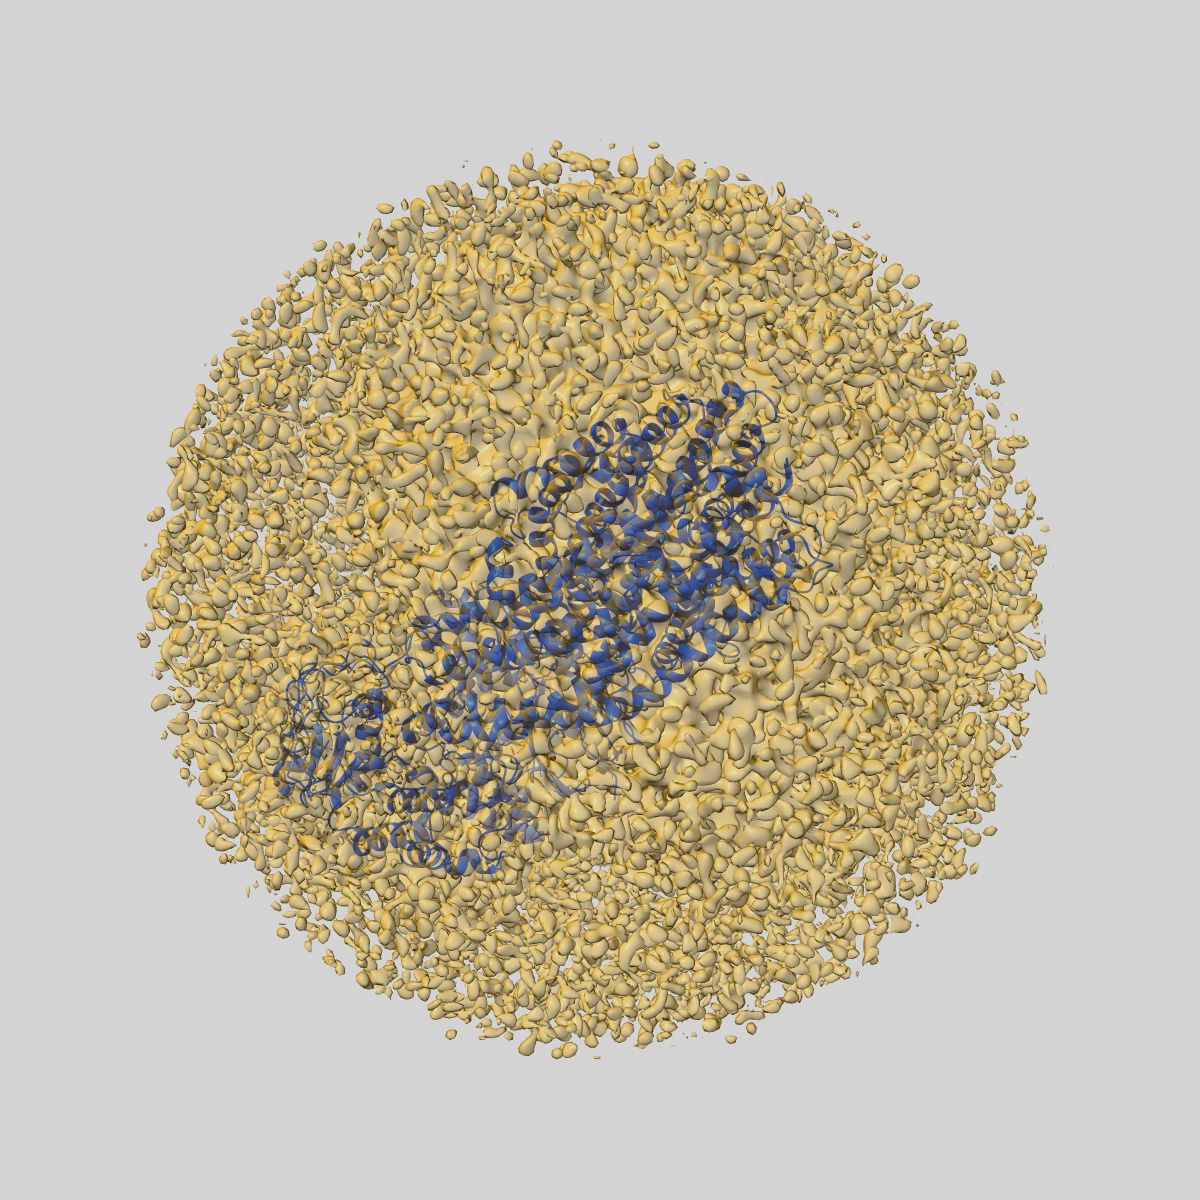

Structure of the cystic fibrosis transmembrane conductance regulator (CFTR) from zebrafish

Sample Organism: Danio rerio

Sample: Cystic fibrosis transmembrane conductance regulator or ABCC7

Fitted models: 5uar

Deposition Authors: Zhang Z, Chen J

Atomic structure of the cystic fibrosis transmembrane conductance regulator

Zhang Z, Chen J

(2016) Cell , 167 , 1586 - 1597